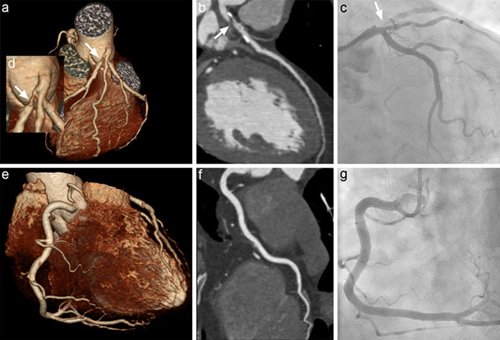

冠心病的診斷

目前診斷冠心病的方法很多,如心電圖檢查、超聲心動圖、CT檢查等都可以間接反映冠狀動脈有沒有病變。冠狀動脈造影術(shù)是目前能直接觀察到冠狀動脈病變部位、狹窄程度和遠(yuǎn)端血流通暢情況等,并測定左心室功能的診斷方法。